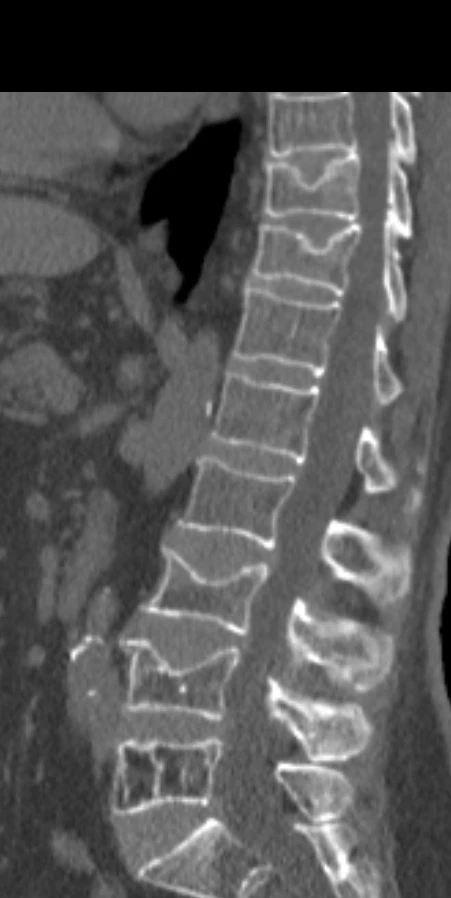

Ещё один прекрасный пример стойкости позвонков, в которых имеется гемангиома, у которой, в свою очередь, имеются очень крупные и плотные трабекулы, по всей видимости, они и не дают позвонку сломаться даже при развитии остеопороза. Пациенту 65 лет, множественные патологические переломы позвонков на фоне остеопороза, а позвонок с гемангиомой практически не изменён. К вопросу о профилактическом цементировании…